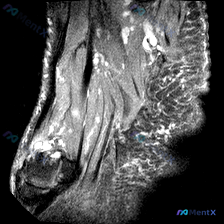

今天分享一例踝关节MRI读片,原问题聚焦软骨异常,整理了完整的影像分析和诊断思路,供大家讨论。 一、完整影像所见 这是踝关节MRI矢状位T2加权图像,所见如下: 1. 骨骼:胫骨远端、距骨、跟骨等结构形态完整,无明确骨折线;但距骨体中心及后部可见大片边界模糊的弥漫性高信号,跟骨前上部也可见散在高信号...